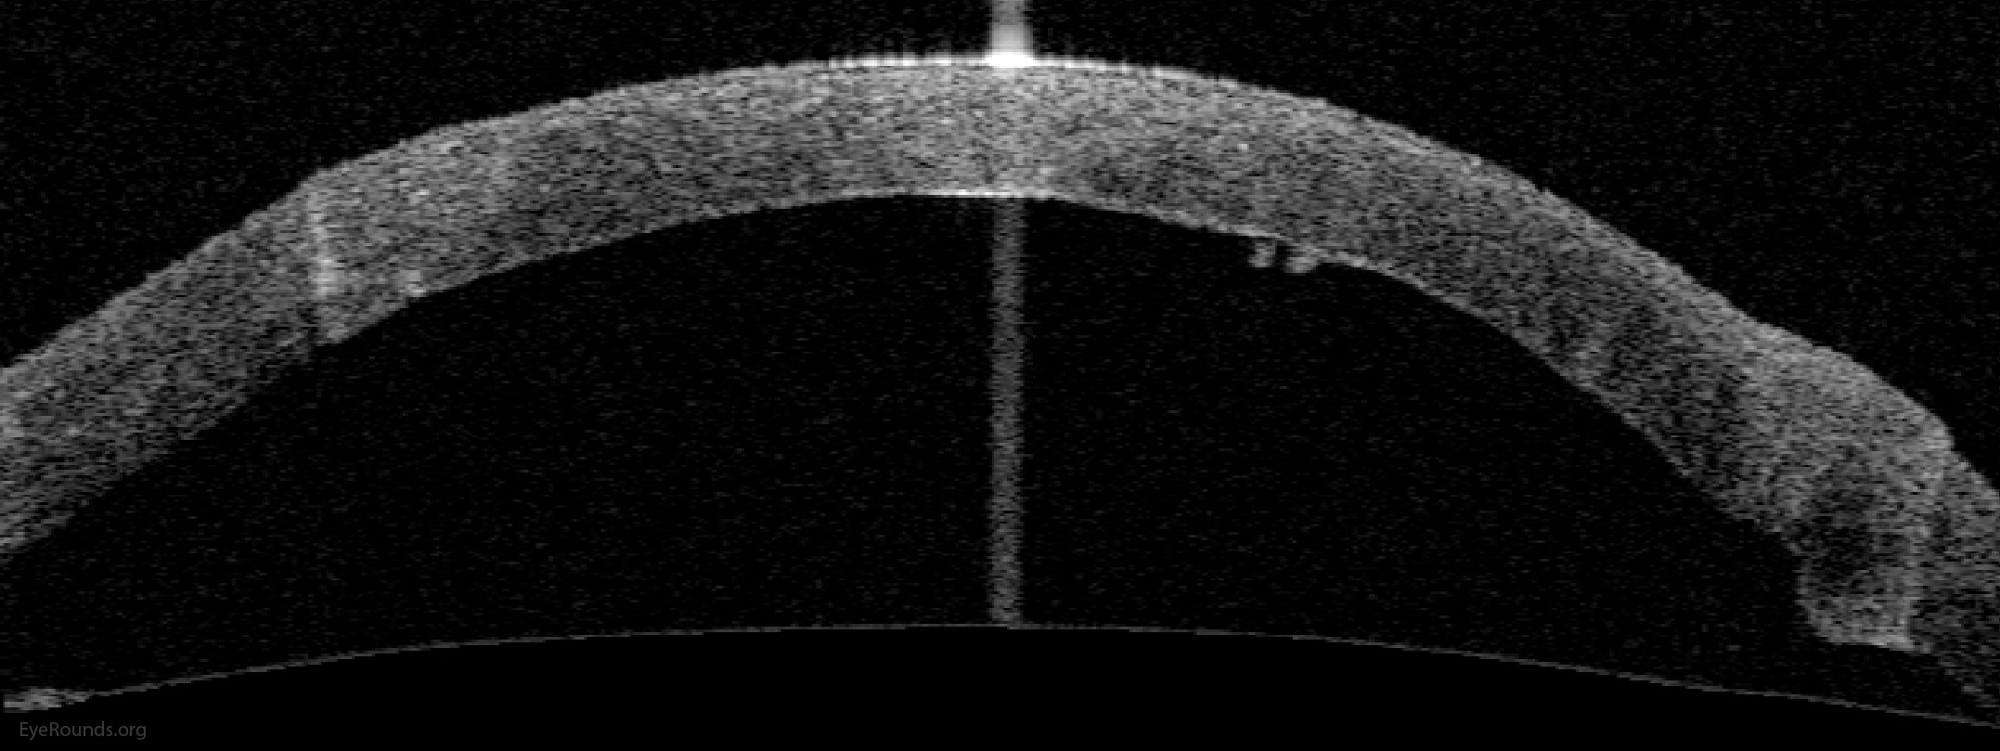

DALK is a partial-thickness cornea transplant procedure that involves selective transplantation of the corneal stroma, leaving the native Descemet membrane and endothelium in place. A trephine of an appropriate diameter is used to make a partial-thickness incision into the patient's cornea, followed by pneumodissection or manual dissection of the anterior stroma. This is followed by placement of a graft prepared from a full-thickness punch in which the donor endothelium-Descemet membrane complex has been removed. The intention is to preserve the patient's Descemet membrane and endothelium. Similar to PK, the graft is secured with interrupted and/or running sutures (Figure 5) and these are then selectively removed post-operatively (Figure 6).

DALK is useful for processes involving the corneal stroma in the presence of healthy endothelium. Examples include corneal ectasia (such as keratoconus in the absence of hydrops), corneal scars that are not full-thickness, and corneal stromal dystrophies (1, 15, 16).

Because it is not a full-thickness procedure, the resultant wound is stronger than that of a PK. Leaving the host endothelium intact significantly decreases the risk of endothelial rejection.

The surgery is more complex and difficult to perform than PK. If the Descemet membrane is perforated intraoperatively, the surgeon must convert to a PK. The "big bubble" technique makes dissection more consistent and is the preferred technique at our institution (12).